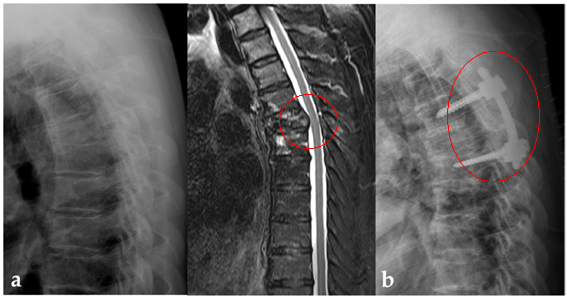

비소세포폐암이 척추로 전이된 환자 중 표적항암제 치료가 가능한 돌연변이 유전자를 가진 환자는 상대적으로 생존율이 높기 때문에, 척추 전이암 수술도 적극적으로 고려해야 한다는 연구 결과가 발표되었다.

척추 전이암이 진행되면 환자의 거동이 어려워지고 생존율 저하로 이어지기 때문에 적극적 치료가 고려된다. 하지만 원발암 종류와 환자마다 전신 상태가 다르기 때문에 여전히 척추 전이암을 수술로 치료할지 여부는 쉽지 않은 결정이었다.

2011년부터 2017년까지 비소세포폐암의 척추 전이로 척추 수술과 방사선 치료 병합 요법을 시행한 22명을 선정하였다.

이 후 환자를 나이, 성별, 기대 수명, 척추 불안정성을 고려한 1:1로 경향 점수 대응을 통해 방사선 단독 치료만 진행한 시행한 231명 중 비슷한 조건의 22명과 비교하였다.

방사선 단독 치료 군에서만 5명의 환자(22.7%)가 병적 골절로 인한 신경학적 증상의 악화가 관찰되었다. 또한 수술과 방사선 치료를 시행한 군에서는 보행이 불가능했던 4명의 환자가 보행이 가능하게 되었으며, 5명의 환자는 신경학적 증상이 개선되었다.

전이암은 보통 4기로 진단되며, 원발암에 대한 폐암 치료와 전이암은 방사선 치료가 우선이지만, 전이된 척추뼈의 불안정성이 있거나 신경을 압박하여 마비를 일으키면 수술적 치료가 필요하다.